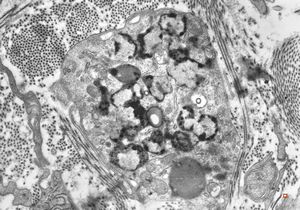

M,40y. | granular cell tumor

F,30y. | granular cell tumor